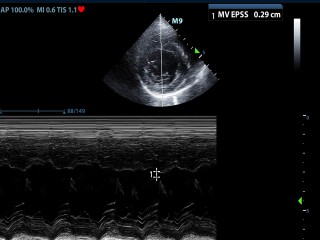

Echografie hart

Toen onze oude echoapparaat vervangen moest worden hebben we ervoor gekozen dat bij ons nieuwe echo apparaat het ook mogelijk moest zijn om echo onderzoeken van het hart te maken. Er moet dan o.a. doppler opzitten en je moet een ECG kunnen aansluiten, ook zijn de eisen voor de kwaliteit veel hoger. Onze nieuwe Mindray M9 voldoet aan deze eisen en heeft een zeer gevoelige en nauwkeurige echo detectie.

Dierenarts Rianne Compagner maakt de hartecho's, zij heeft diverse cursussen en nascholingen hiervoor gevolgd.

Hieronder zie je een aantal foto's van het hart.